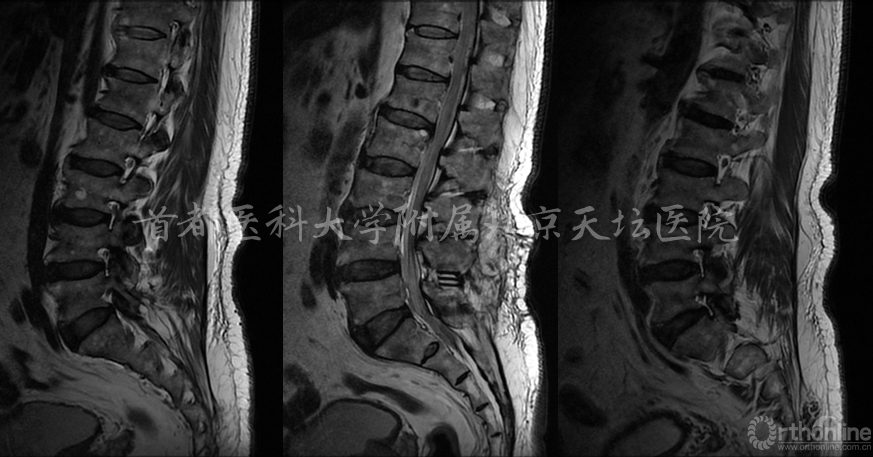

影像资料: